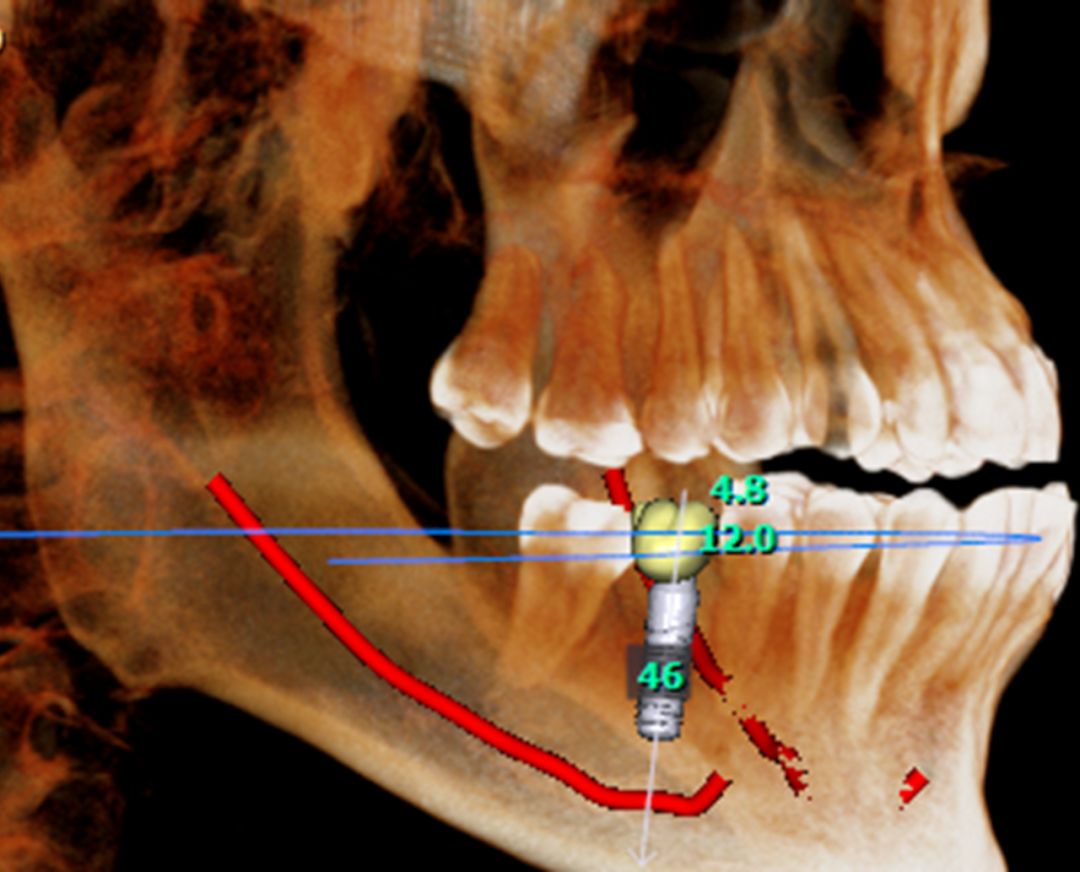

“伯爵Bondream”智能3D全景CBCT 多金屬去偽影圖

OnDemand 3D后處理軟件直接模擬真實(shí)種植場(chǎng)景,更有骨密度精確測(cè)量,醫(yī)患溝通更直觀,手術(shù)更安全,患者更信任。

骨密度精確測(cè)量